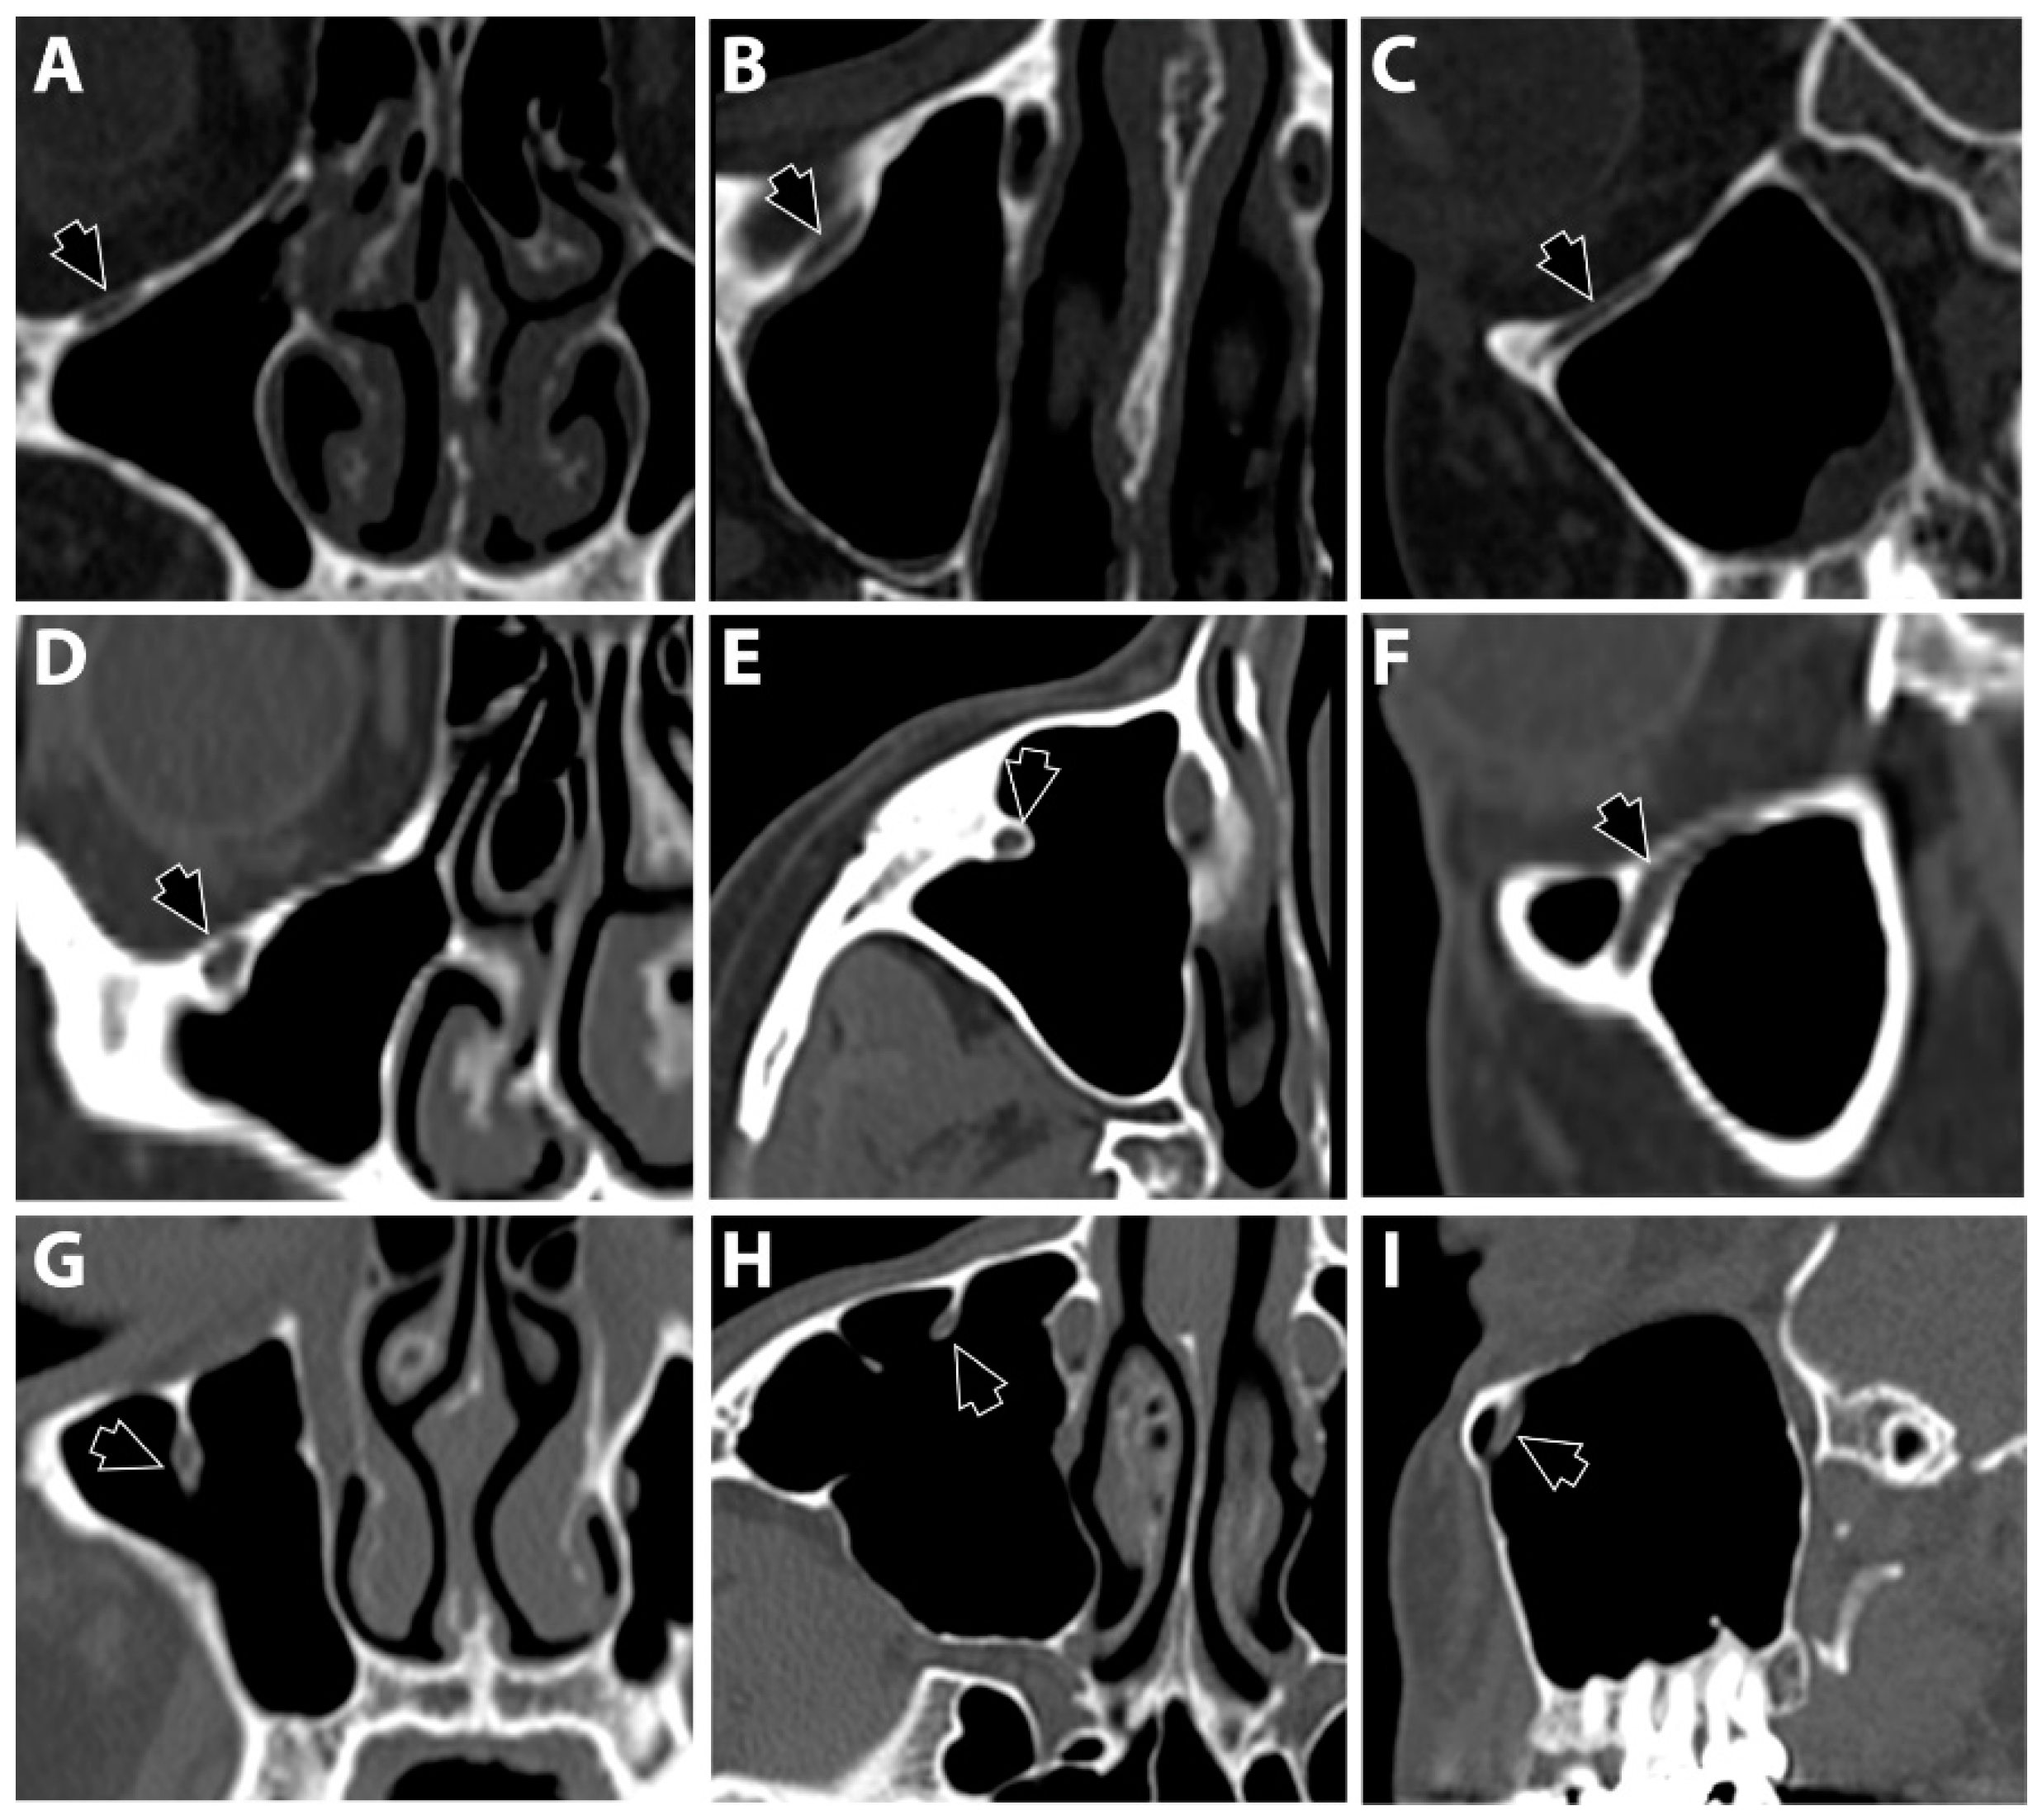

2.1. Infraorbital Ethmoid Cells

2.2. Infraorbital Canal Location